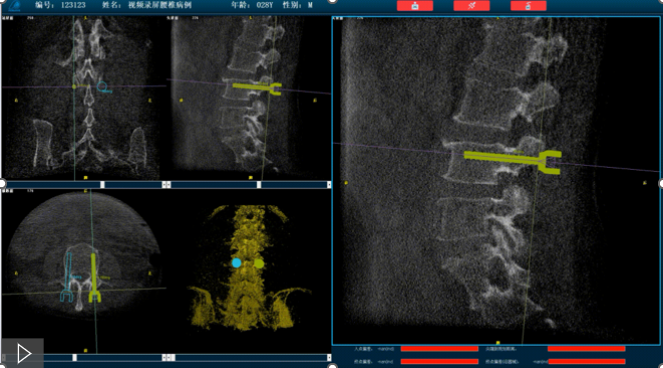

首先,需要明确的是机器人手术,机器人在术中还是做辅助性操作,术前基于三维C形臂等影像扫描得到骨骼结构的三维数据,机器人系统利用手术规划软件,引导医生进行可视化预手术规划(钉道规划、入钉角度),选择合适的螺钉规格、尺寸,辅助评估和及时调整手术路径规划设计,整台手术都是在主刀医生的把控下进行操作的?;魅讼低巢唤隹科祝一固嵘耸质醯陌踩?、机械臂的精准以及力传感识别、实时动态追踪等?;ぜ际酰黾恿耸质醯淖既沸院桶踩?。

就以普爱医疗骨科机器人PL300B为例,骨科机器人可以保证亚毫米级精准度,例如在脊柱上植入椎弓根螺钉,传统手术需要暴露骨组织解剖结构,往往会有10-20cm的开口,而使用了手术机器人可以将开口转变为数个1-2cm的开口,出血量降低至95%以上,大大降低并发症的发生率,同时有益于病患的更快的术后恢复。